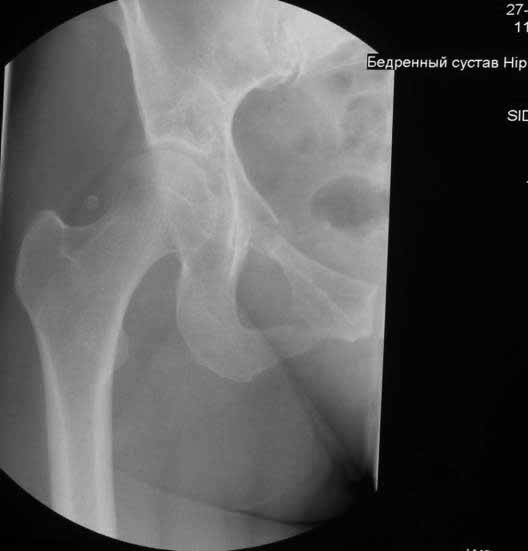

Уважаемые коллеги. Хотелось бы услышать мнения и советы по представляемому случаю. Пациентка 45 лет. Бесцементное эндопротезирование левого тазобедренного сустава 6 лет назад (впадина RM, Mathys, металл-металл, ножка Зульцеровская). За 10 лет до протезирования – коррегирующая остеотомия бедренной кости, которая не срослась в течение года до удаления пластины, а затем срослась в течение 3 месяцев иммобилизации в кокситной повязке. После протезирования получилось наблюдать пациентку почти постоянно, поскольку через 2 года синтезировал ей лодыжки на оперированной стороне, затем, через несколько месяцев удалил фиксаторы, а в 2009г. резецировал мениск на противоположной стороне. Боли все эти годы не беспокоили. Пациентка чуть выше среднего роста, вес тела нормальный. Физические нагрузки переносила хорошо. Работает на 7 этаже без лифта. Год назад экстирпация матки по поводу лейомиомы больших размеров. Несколько месяцев назад появились боли в области левого тазобедренного сустава. При рентгеновском и КТ исследованиях (июль с.г.) – нестабильность тазового компонента. От предложенной замены протеза пациентка на тот момент, слава богу, отказалась. Через какое то время боли в области левого тазобедренного сустава практически полностью прошли, а около 2 месяцев назад появилось ощущение патологической подвижности таза и боли в паху справа, которые через некоторое время уменьшились, а потом снова усилились после значительных физических нагрузок (много ходила по песку на пляже, носила тяжести). Ежедневно принимала диклофенак. На рентгенограммах – переломы правой лонной кости. Сейчас госпитализирована из-за болей в паху справа. Боли слева не беспокоят. На фоне снижения нагрузок в стационаре боли значимо уменьшились. Способна ходить без средств дополнительной опоры.В анализах крови чуть повышены трансаминазы и гамма-ГТ, моча без особенностей.

Вопросы: -правильно ли я расцениваю переломы как стрессовые на фоне неполноценного таза (pelvic insufficiency stress fractures)? -Можно ли так же расценить ситуацию на стороне протеза и, соответственно, не торопиться с ревизией, рассчитывая на вторичную стабилизацию? Уж больно не хочется менять ножку. -Если думать о ревизии, то когда? На представленных снимках тазобедренный сустав до и сразу после операции, затем 2 снимка 2009г., когда ничего не беспокоило, затем КТ 2-х месячной давности и вчерашние рентгенограммы обоих тазобедренных суставов.

Уважаемый Сергей,

Похоже Вы правы,это напоминает перегрузочный перелом, но вопрос о его причине остается открытым, просто ли это избыточная нагрузка на правую половину таза вследствие нестабильности чашки слева и ограничение нагрузки на левую половину, либо это гормональные изменения, приведшие к изменению метаболизма и перелому. Я бы дождался консолидации и поставил вопрос о замене чашки. Молодая женщина, 45 лет, пока еще можно обойтись достаточно простой манипуляцией, если процесс начался, его не остановить, но дальше будет намного сложнее.